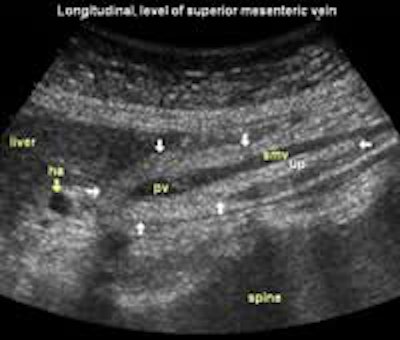

Longitudinal planes from right to left:

![]() Image22 |